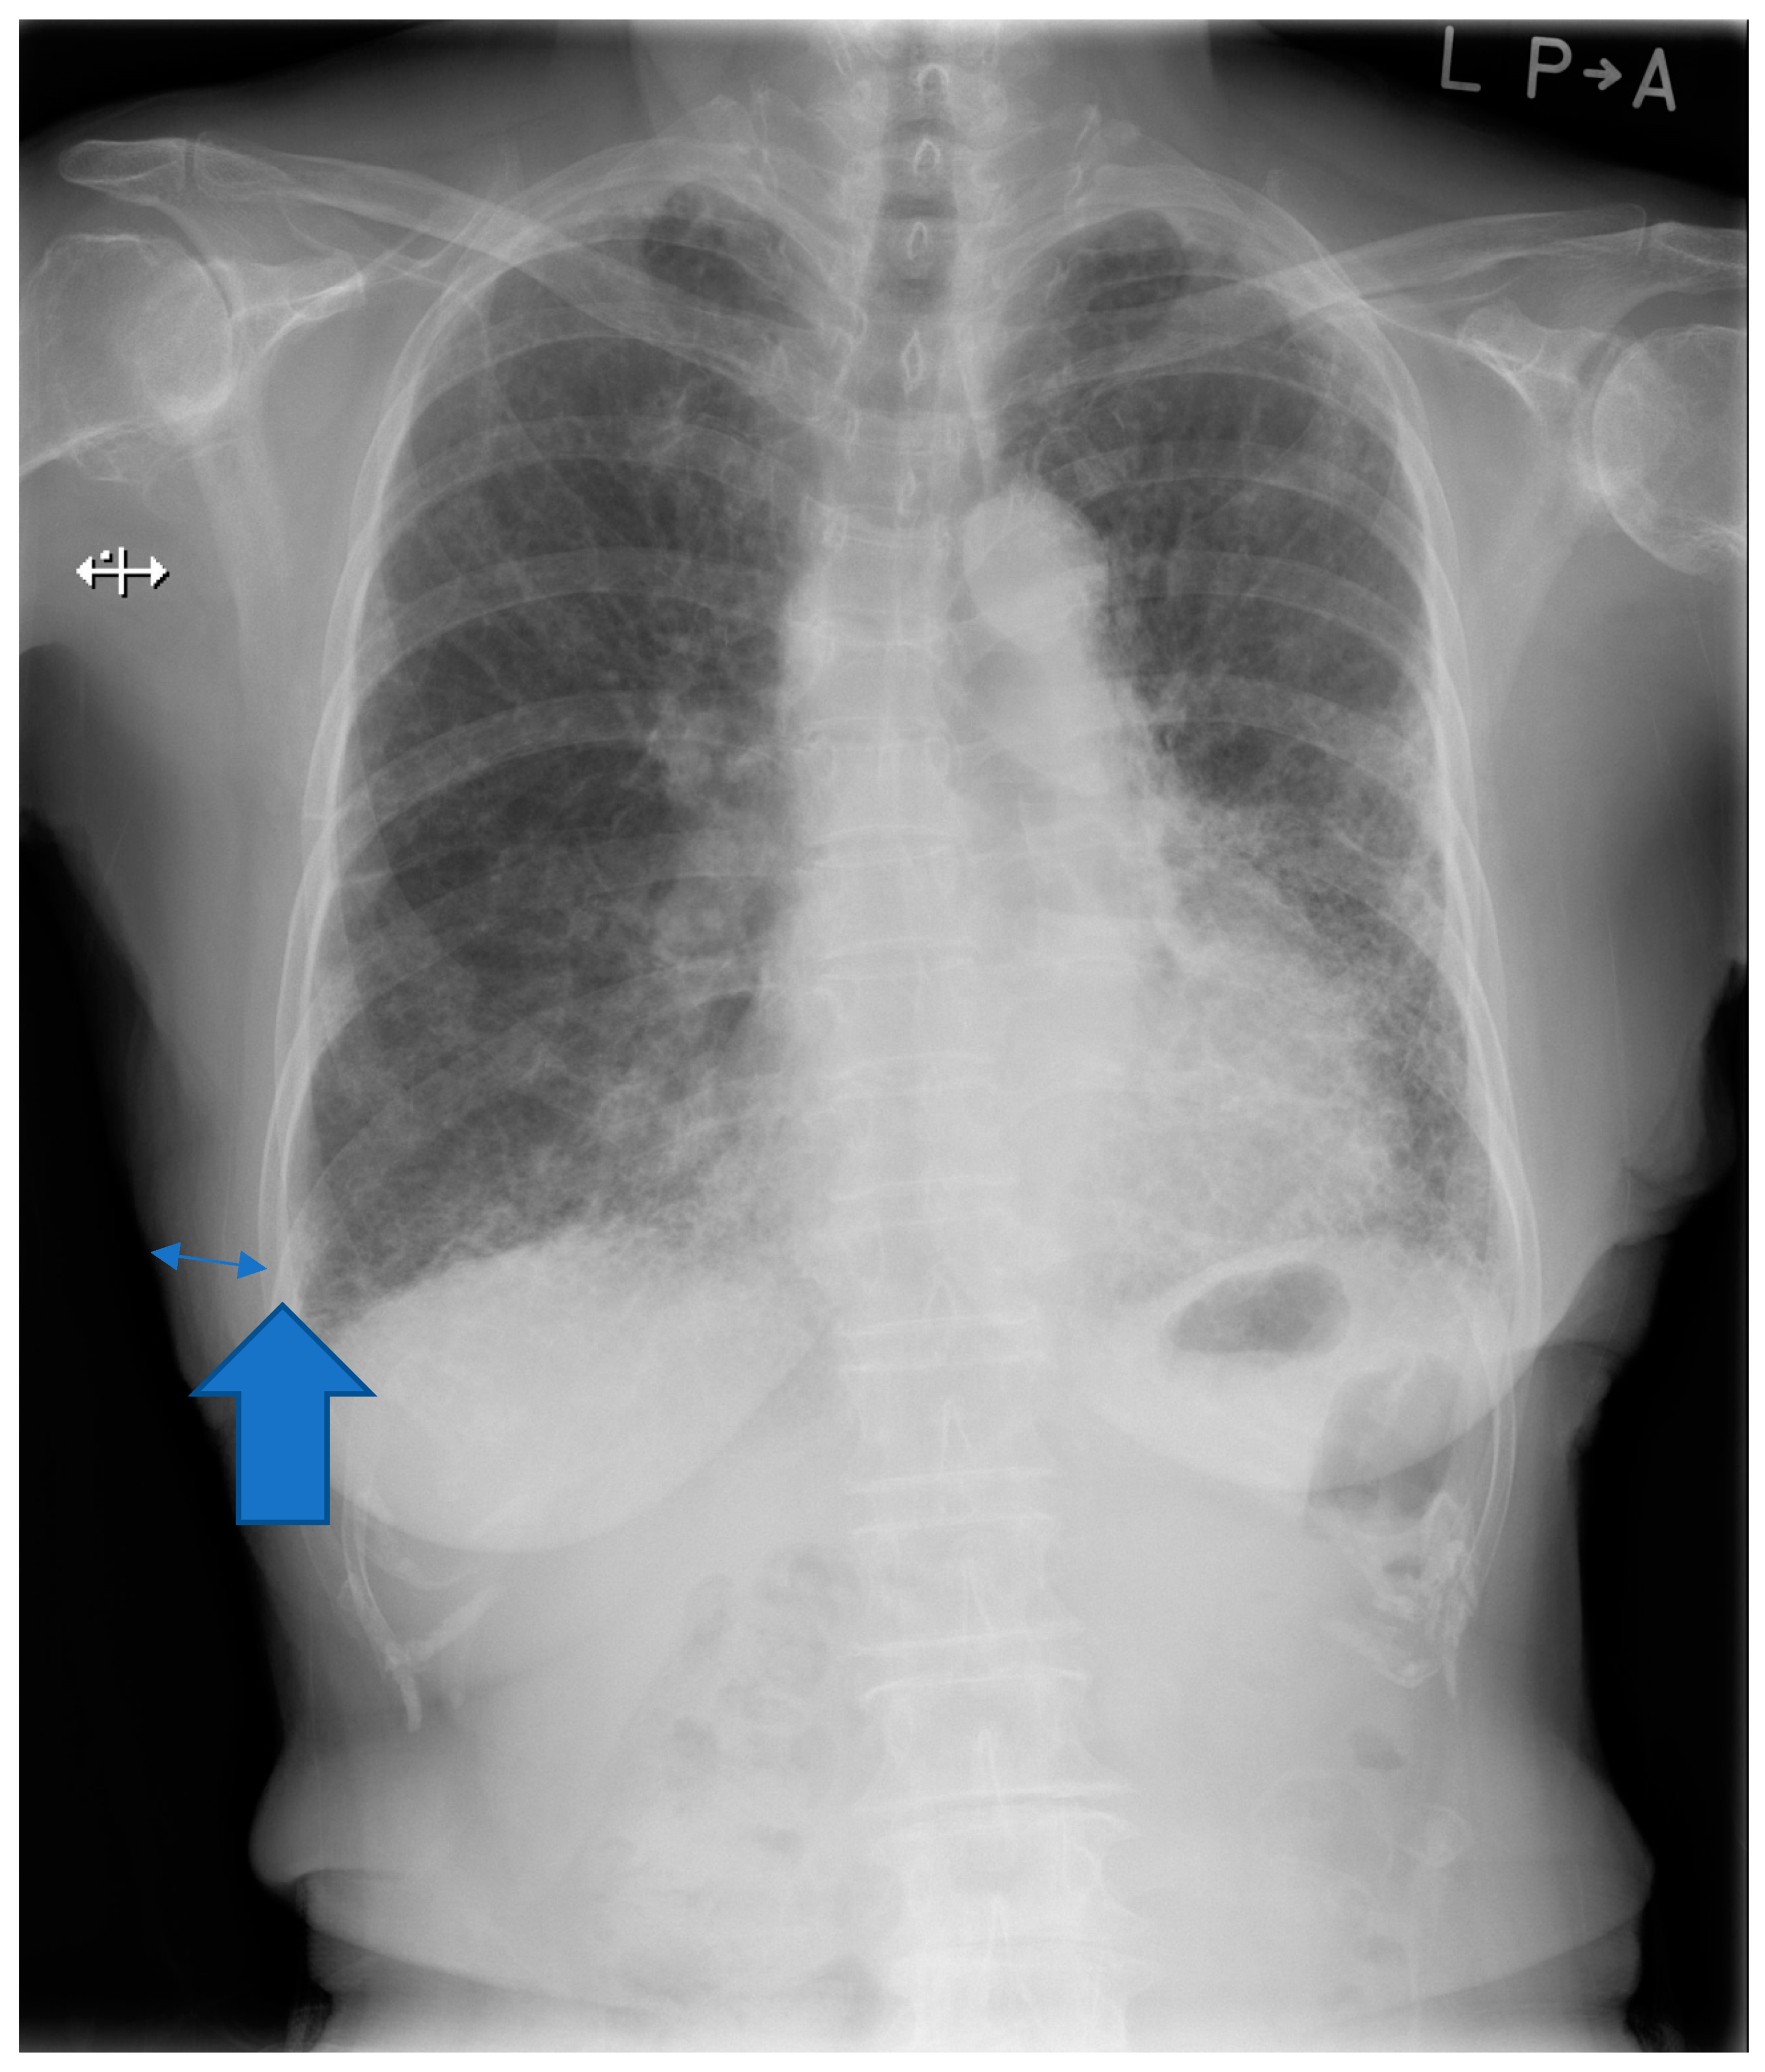

The soft tissue thickness from the chest radiograph of the posterior-anterior view in an erect position was assessed. The positive associations between BMI and progression of IPF were previously described in the literature [17,18]. The soft tissue thickness of the right 9th rib is usually the thinnest in the thoracic cage [19]. The right 9th rib is an adequate anatomical landmark for the evaluation of soft tissue thickness. The measurement of the soft tissue thickness at the right 9th rib is outlined in Figure 1. The distance between the outer edge of soft tissue and that of the right 9th rib was defined as soft tissue thickness measured on the posterior-anterior view. Furthermore, we reviewed the chest high-resolution computed tomography (HRCT) pattern at diagnosis of IPF based on the latest international IPF guideline [20].

Figure 1.

Evaluation of soft tissue thickness in the chest radiograph. Thin double arrow indicates soft tissue thickness. Thick arrow indicates outer edge of the right 9th rib.